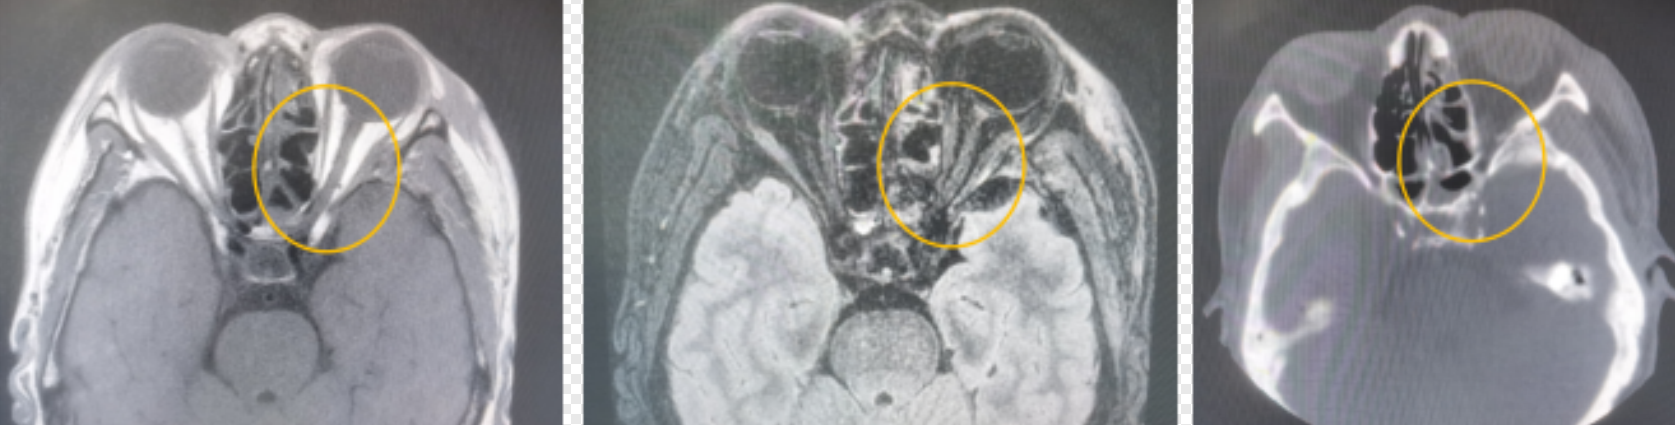

(▲CT提示视神经管骨折片嵌顿视神经,MRI提示损伤的视神经水肿明显)

这根重要的“电缆”必须穿过颅骨上一个名为“视神经管”的骨性管道才能进入大脑。涂女士的外伤导致了视神经管骨折,碎骨片压迫或损伤了管内的视神经,就像被掐住的电线,信号无法传递,从而面临失明风险。